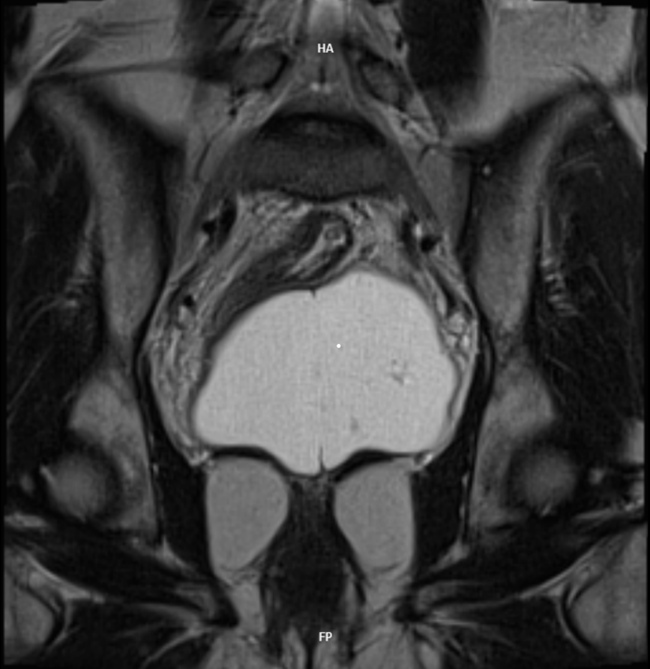

Malignant Rhabdoid Tumor of the Kidney in an 11-Month-Old Child: Case Report and Literature Review

Laura Mendes Lopes, Fabricio Grenteski, Carlos Roberto Naufel Júnior , Guilherme Andrade Coelho, Guilherme Ferrarini Furlan, Nertan Tefilli, José Anderson Feitoza , Igor Luna Peixoto

bjcr13